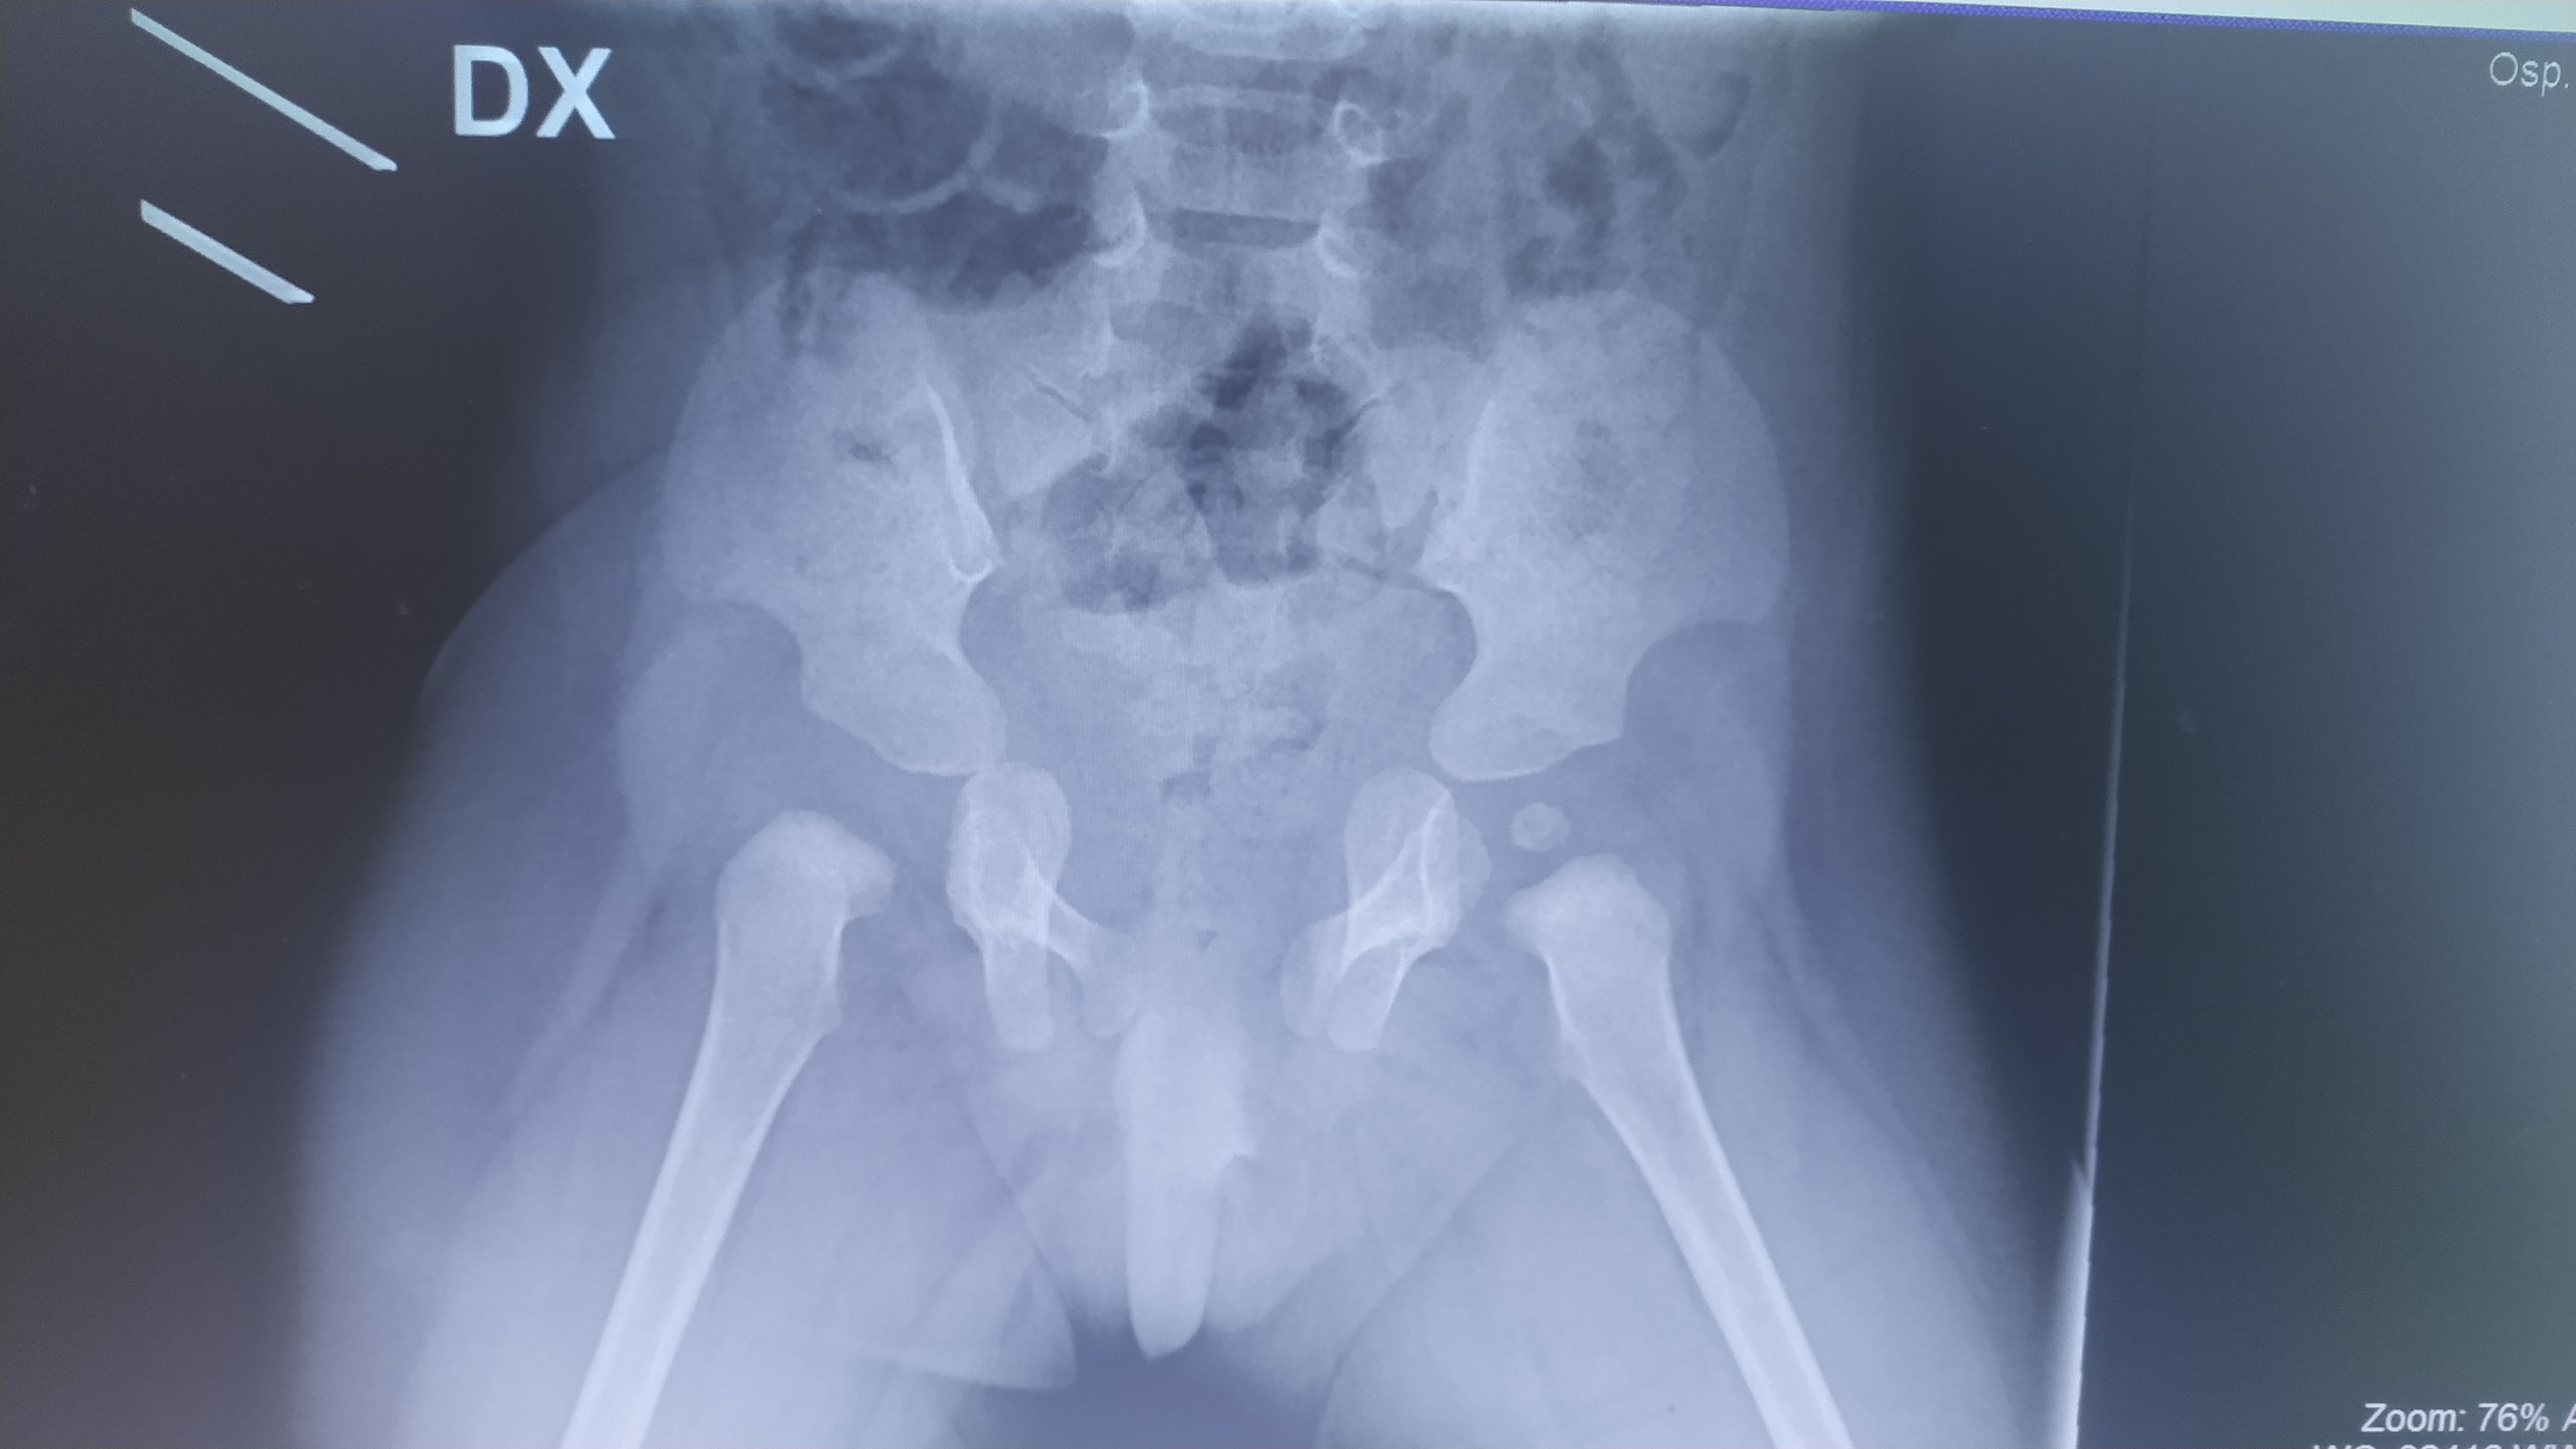

Mia figlia ha 13 mesi ed è reduce da una sublussazione posteriore dx trattata con 1 mese di trazione, poco meno di 4 mesi di gesso e 4 mesi di millgram.

La rx di ieri mostra che le anche sono centrate al 29° dx e 20° sx ma il nucleo dx non è ancora riconoscibile; questo ritardo può essere in qualche modo fisiologico a 13 mesi, e alla luce della storia clinica di mia figlia , o può essere indicativo di una sofferenza dei tessuti?

Commento file: rx di ieri

IMG_20200212_165912.jpg